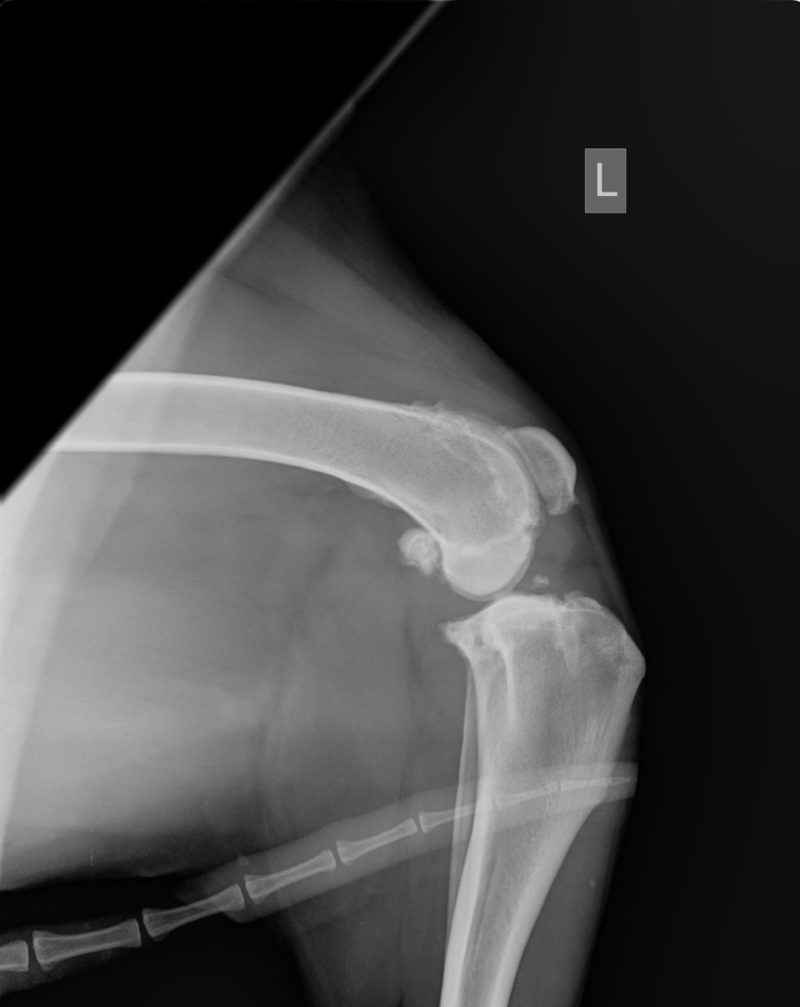

Die Röntgenaufnahmen des Haustierarztes vom linken Knie sowie des Knies und der Hüfte zeigen einen alten Kreuzbandriss (KBR) mit bereits hochgradiger Arthrose des Kniegelenks. Die Knie-Mechanik wird durch die Arthrose vermutlich mehr beeinträchtigt als durch den KBR. Weitere Röntgenbilder liegen nicht vor. Da Lea zudem sehr auffällig in der Wirbelsäule ist, haben wir auch hier Röntgenbilder angefertigt. Auf diesen sind ebenfalls hochgradige Arthrosen sowie ein Bandscheibenvorfall in der hinteren Brustwirbelsäule zu sehen. Das ist wohl momentan Leas hautsächliches Problem. Bei einer Kreuzbandriss-OP mit entsprechender Lagerung und anschließender Schonhaltung wäre die Wirbelsäulen-Problematik möglicherweise noch weiter verschlechtert worden. Das hätte im schlimmsten Fall sogar zu einer vollständigen Lähmung führen können. Zudem sind die mechanischen Beeinträchtigungen im Knie durch die hochgradige Arthrose mit einer Kreuzband-OP nicht aufzulösen. Bei einer Instabilität des Kniegelenks wäre selbstverständlich eine Operation des KBR notwendig. Sofern die Stabilität des Gelenks erhalten ist, können auch durch konservative Behandlungsmethoden oft sehr erfreuliche Ergebnisse erzielt werden. In Leas Fall wäre eine Entfernung der Verkalkungen innerhalb des Gelenks empfehlenswert, sobald sie für eine OP hinreichend stabil ist, da diese „Fremdkörper“ im Gelenk immer wieder Entzündungen auslösen können.